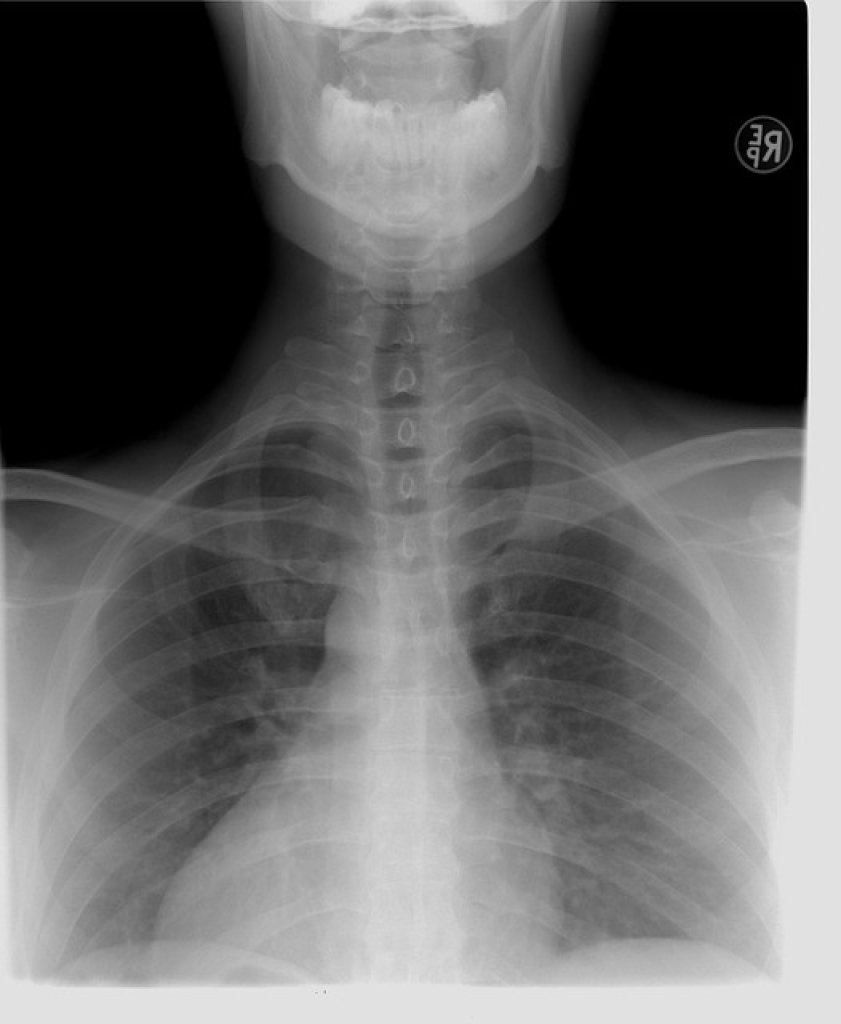

肺癌在台灣素有「三冠癌王」惡名,不僅發生人數多、死亡率高,且晚期確診比例更是居高不下,對國人健康構成重大威脅。胸腔科醫師蘇一峰沉重指出,這就是肺腺癌最可怕之處:「初期症狀不明顯,如果等到有症狀就醫時,十之八九通常都已經是末期!」他甚至分享有病患肺腺癌長到10公分,初期竟仍無明顯警訊。

醫師黃軒也將肺癌比喻為「沉默的獵人」,潛伏在胸腔深處,沒有疼痛、沒有警訊,等到民眾以為只是小感冒時,癌細胞早已築起堅固堡壘。根據國際研究,全球超過80%的肺癌患者在確診時已是第三或第四期。這意味著肺癌並非突然惡化,而是我們太晚察覺。